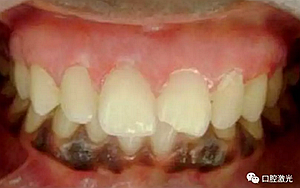

患者22歲,女性,主訴牙齦發(fā)黑??谇粰z查顯示牙齦部位呈黑色,但軟組織健康,沒有表皮粗糙或水腫現(xiàn)象。計(jì)劃使用半導(dǎo)體激光進(jìn)行治療。手術(shù)前患者無需表麻或局麻。采用光纖接觸方式,激光功率設(shè)定為1.5W至2W,連續(xù)模式。氣化黑色牙齦區(qū)域上皮組織。不斷重復(fù)該過程,直至足夠深度的牙齦軟組織表皮被去除干凈?;颊咝g(shù)后需采用漱口水進(jìn)行口腔護(hù)理。

術(shù)前